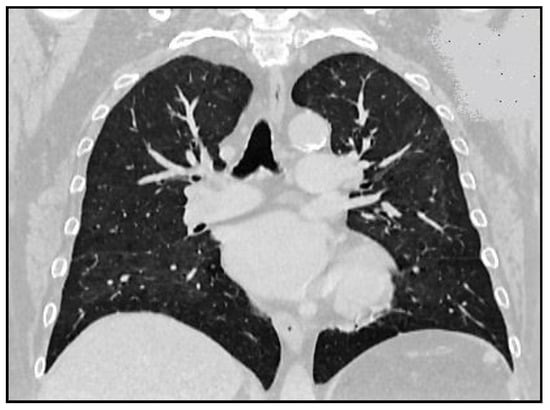

One month later, the patient was reevaluated by chest CT, which showed complete resorption of interstitial lesions and preexisting infiltrates (Figure 3).

Figure 3.

Chest computer tomography scan—one month after Imatinib discontinuation.

Considering the complete resorption of lesions, the problem of resuming Imatinib therapy to treat the HES was posed. Ten days after resumption of treatment with Imatinib 100 mg/day, the patient exhibited progressive exertional dyspnea and hypoxemia (SaO2 on room air = 90%), which is why she was reassessed by chest CT that evidenced the reappearance of interstitial lesions. Imatinib treatment was stopped once again and administration of corticotherapy (Prednisone 15 mg/day) was continued, treatment under which the pulmonary lesions remitted in 2 weeks.